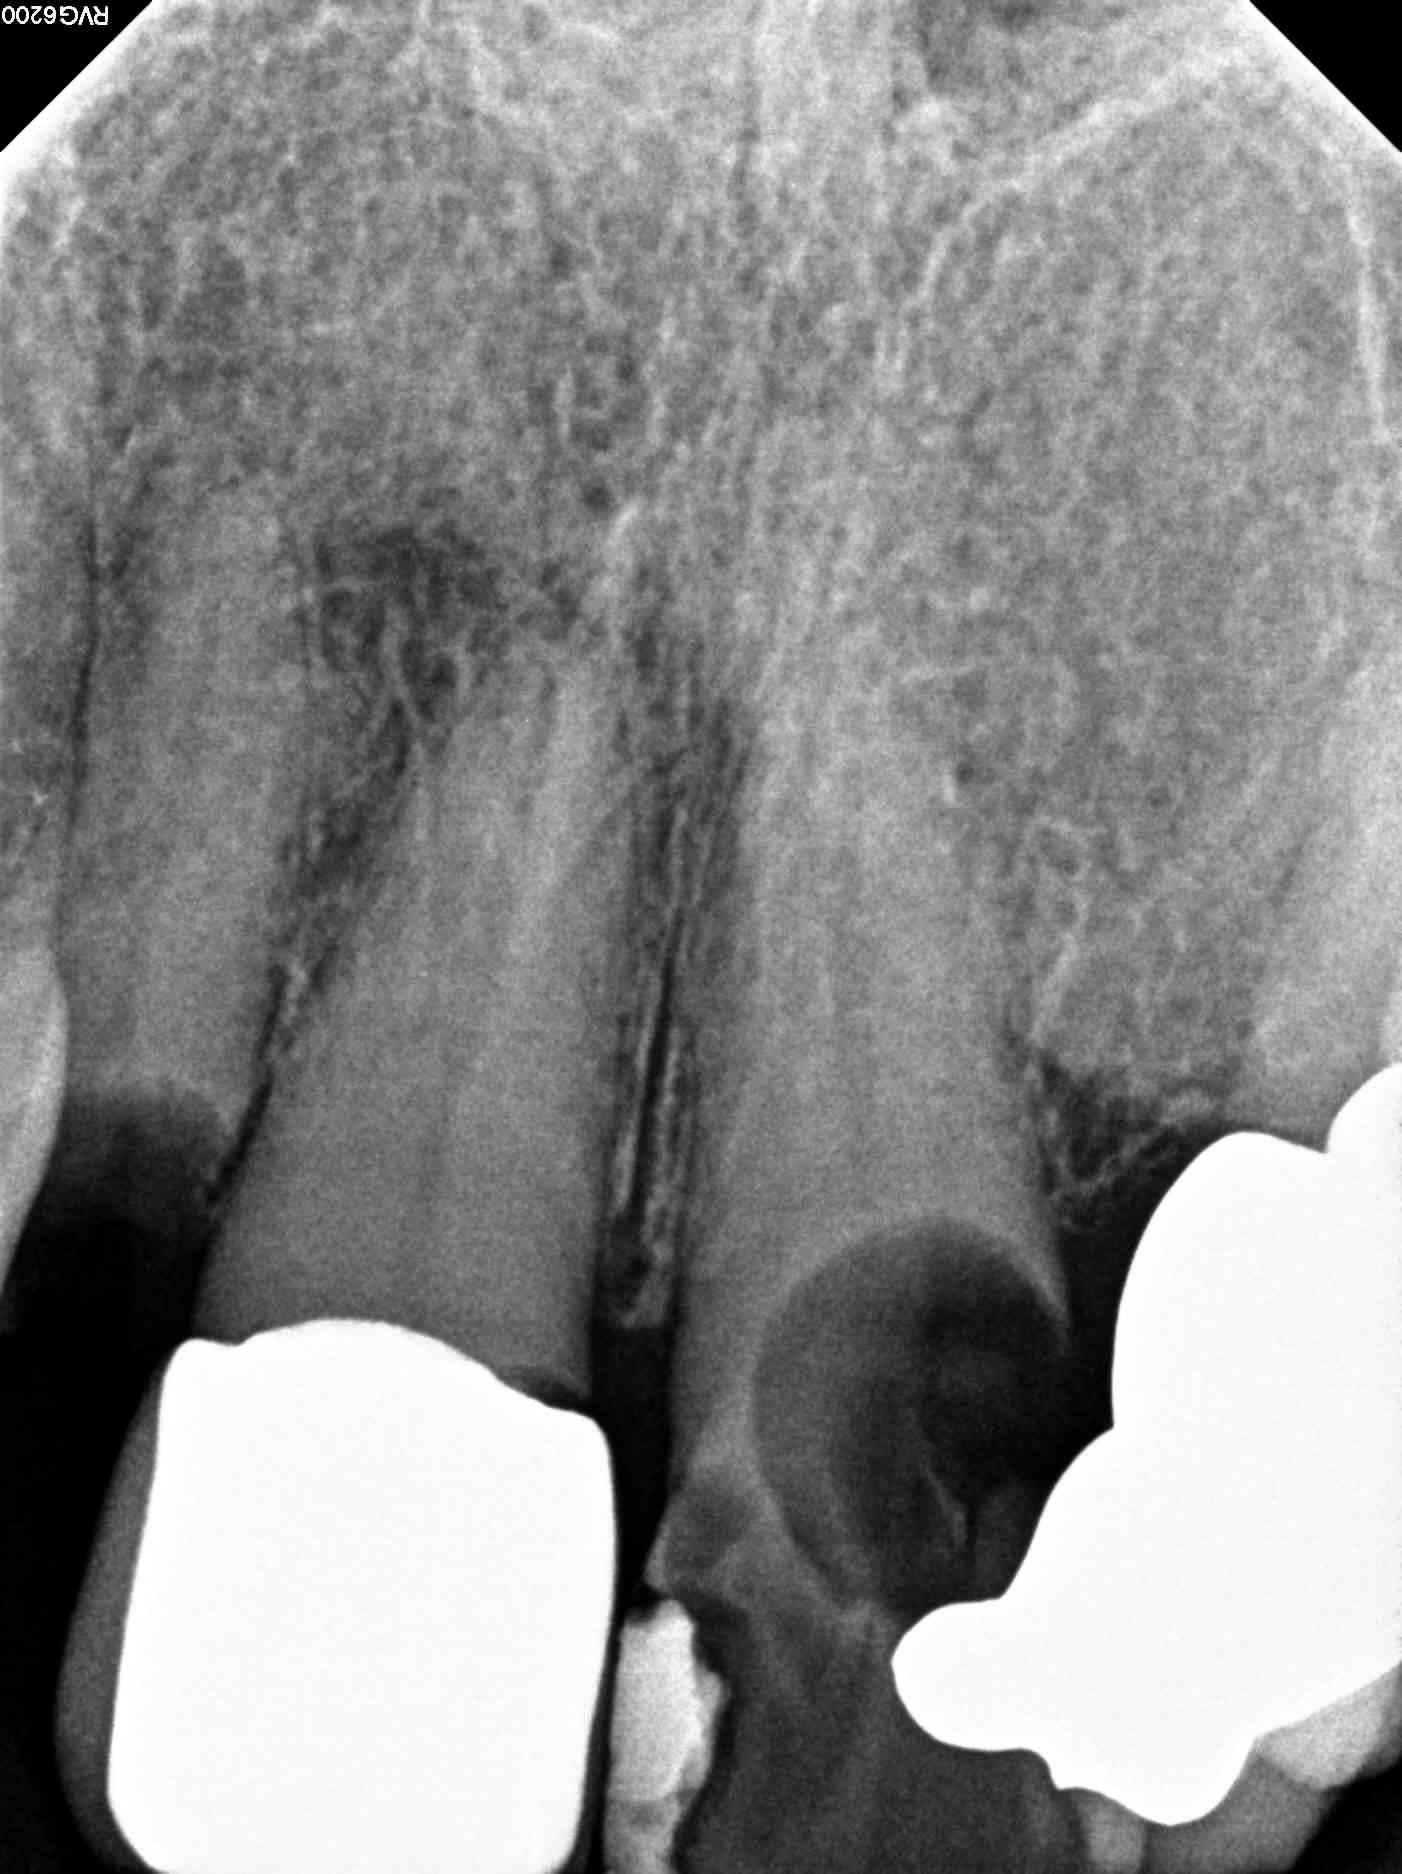

Our geriatric patient had a heavily restored dentition and things were falling apart for her. She needed something both durable and reliable. For teeth #7 and #9, both non-restorable, the best option was immediate dental implant placement and temporary crowns. The teeth were atraumatically extracted and based on the CBCT that was done at our office it was deemed that her bone quantity and quality was sufficient for her to get immediate implants. The case is still in progress and we attached X-rays in this blog of the immediate post-op result. She will be returning in 4 months for final impressions for her dental implants.